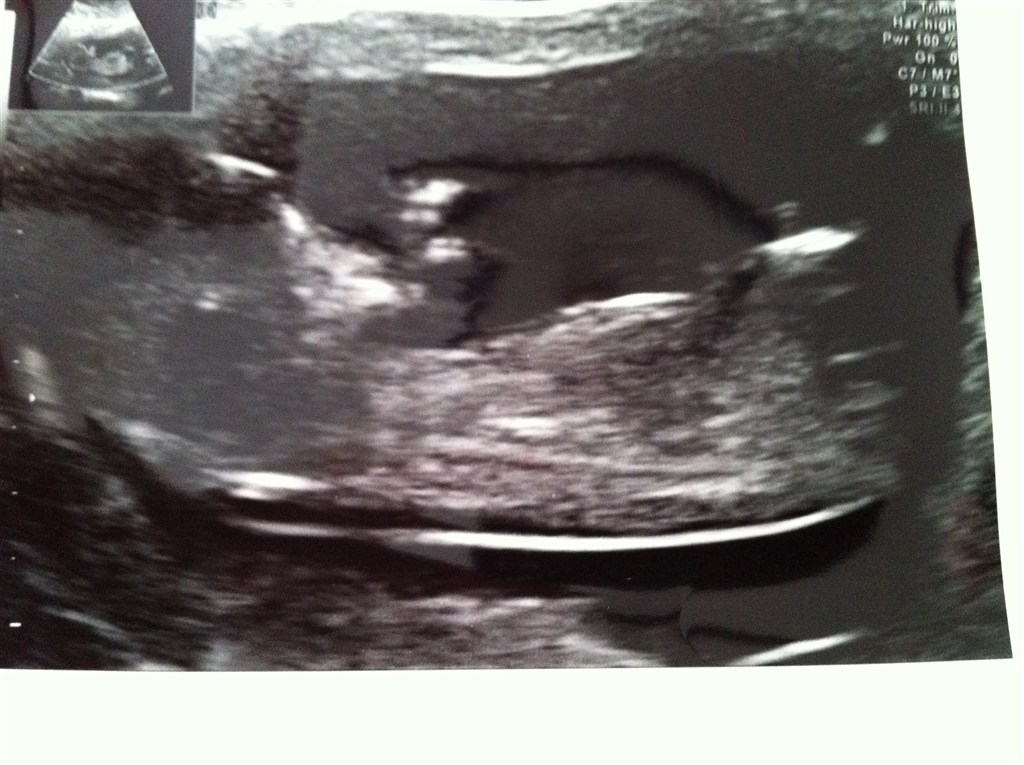

Billedspam af Nakkefoldsscanning i dag den 11.06.2012.

Har været til nakkefoldsscanning i dag og det var godt nok ubeskrivelig den oplevelse, kunne ligge der i flere timer, hvis jeg fik lov hehe. Vores guldklump er alledere 10 cm

Vedhæftede fotos (klik for at se i fuld størrelse)